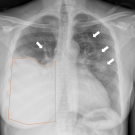

A 63-year-old man developed acute bilateral lower extremity weakness and numbness immediately following a percutaneous lung biopsy.